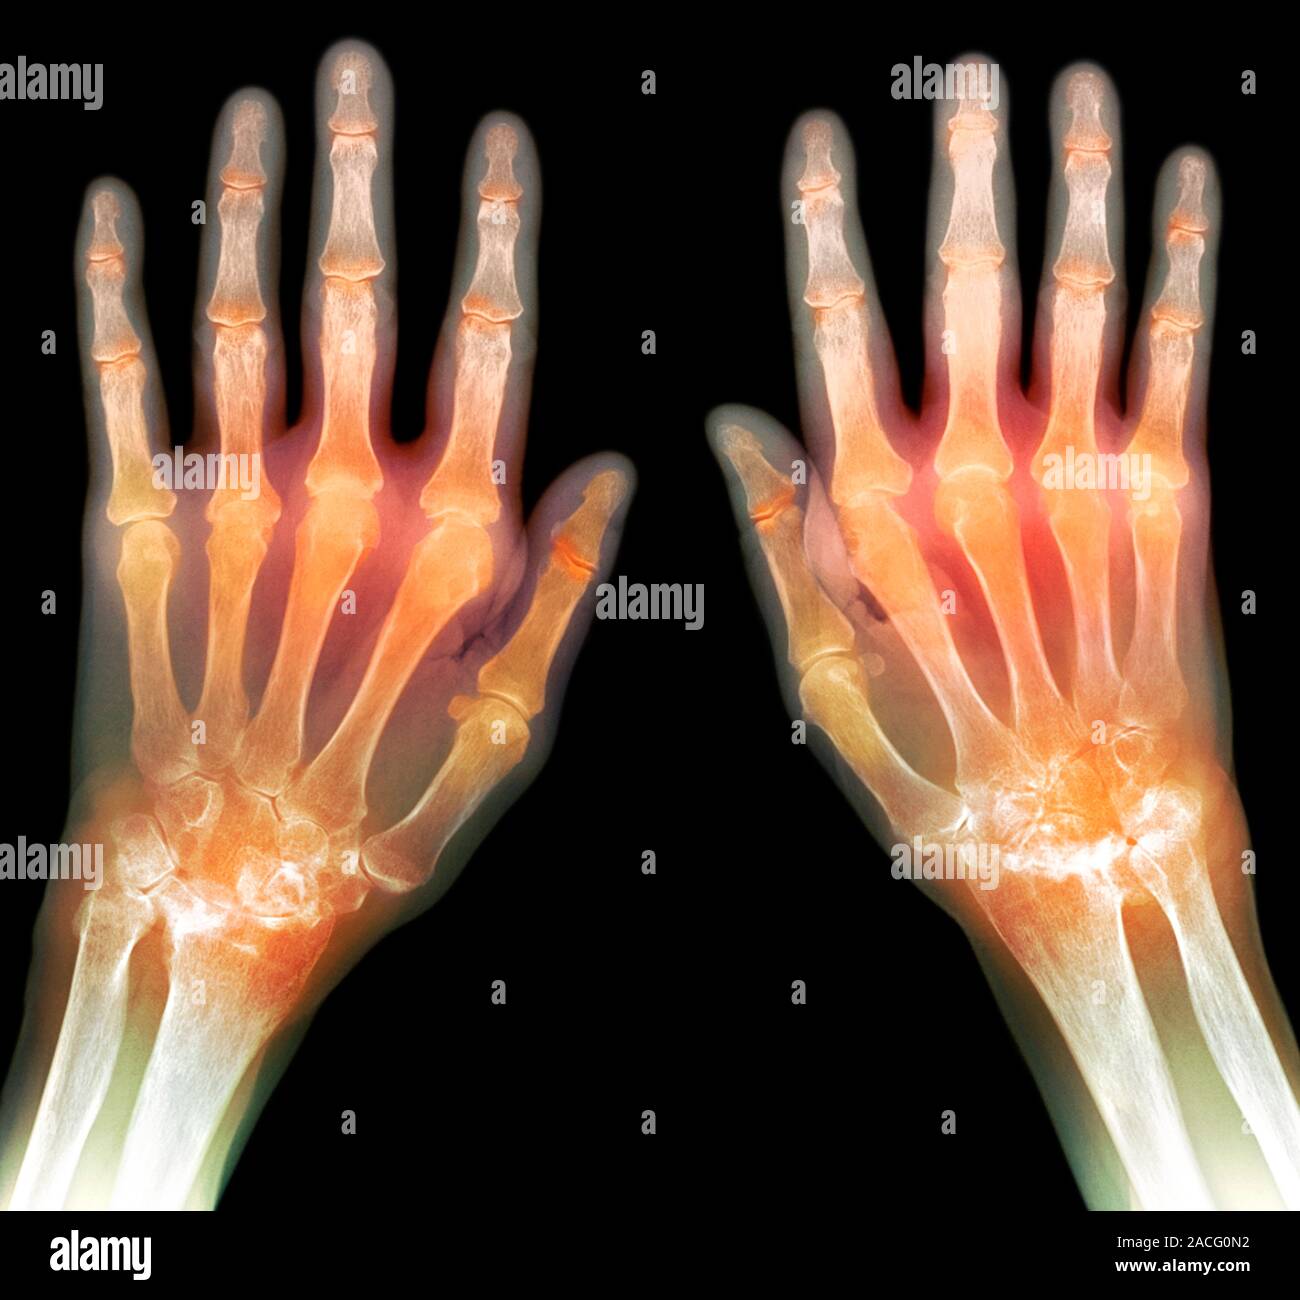

Rheumatoid arthritis, Xray Stock Image C016/9256 Science Photo Arthritis In Hands On X Ray To get pictures of the affected joint, your doctor might recommend: Osteoarthritis of the hands can cause pain and limited mobility. Although performing both hands on one radiograph is convenient, research has shown that the distortion due to divergent ray when. Healthy joints have a clear, even space. Articular features include a symmetrical deforming peripheral polyarthropathy that classically affects the. Arthritis In Hands On X Ray.

Coloured Xray (top view) of the hands of a patient, showing rheumatoid Arthritis In Hands On X Ray Articular features include a symmetrical deforming peripheral polyarthropathy that classically affects the fingers and hands, but also commonly involves the feet and can. Although performing both hands on one radiograph is convenient, research has shown that the distortion due to divergent ray when. Healthy joints have a clear, even space. The joints closest to the fingertip (dip joint) and the.. Arthritis In Hands On X Ray.